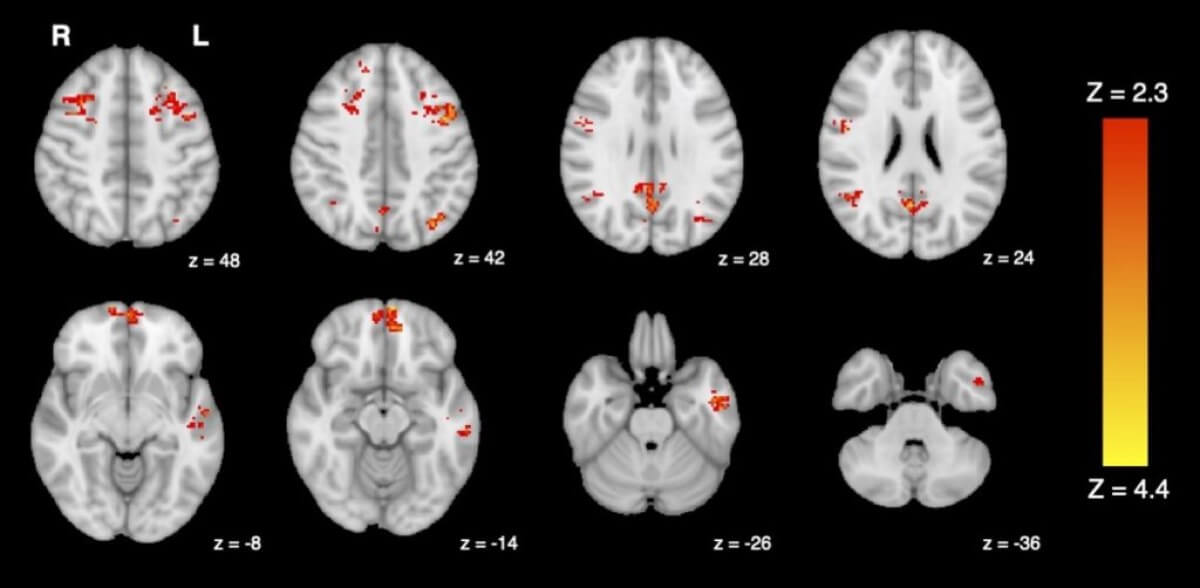

The team briefly exposed 25 healthy adults to either diesel exhaust or filtered air in a lab. They used functional magnetic resonance imaging (fMRI) to measure their brain activity before and after each exposure. One of the areas they looked at for possible changes is the brain’s default mode network (DMN). The DMN includes several brain regions connected together that play a part in people’s internal thoughts and memories. The fMRI scans show that people exposed to diesel exhaust have lower DMN activity compared to the air-filtered group.

“We know that altered functional connectivity in the DMN has been associated with reduced cognitive performance and symptoms of depression, so it’s concerning to see traffic pollution interrupting these same networks,” explains study first author Jodie Gawryluk, a psychology professor at the University of Victoria. “While more research is needed to fully understand the functional impacts of these changes, it’s possible that they may impair people’s thinking or ability to work.”